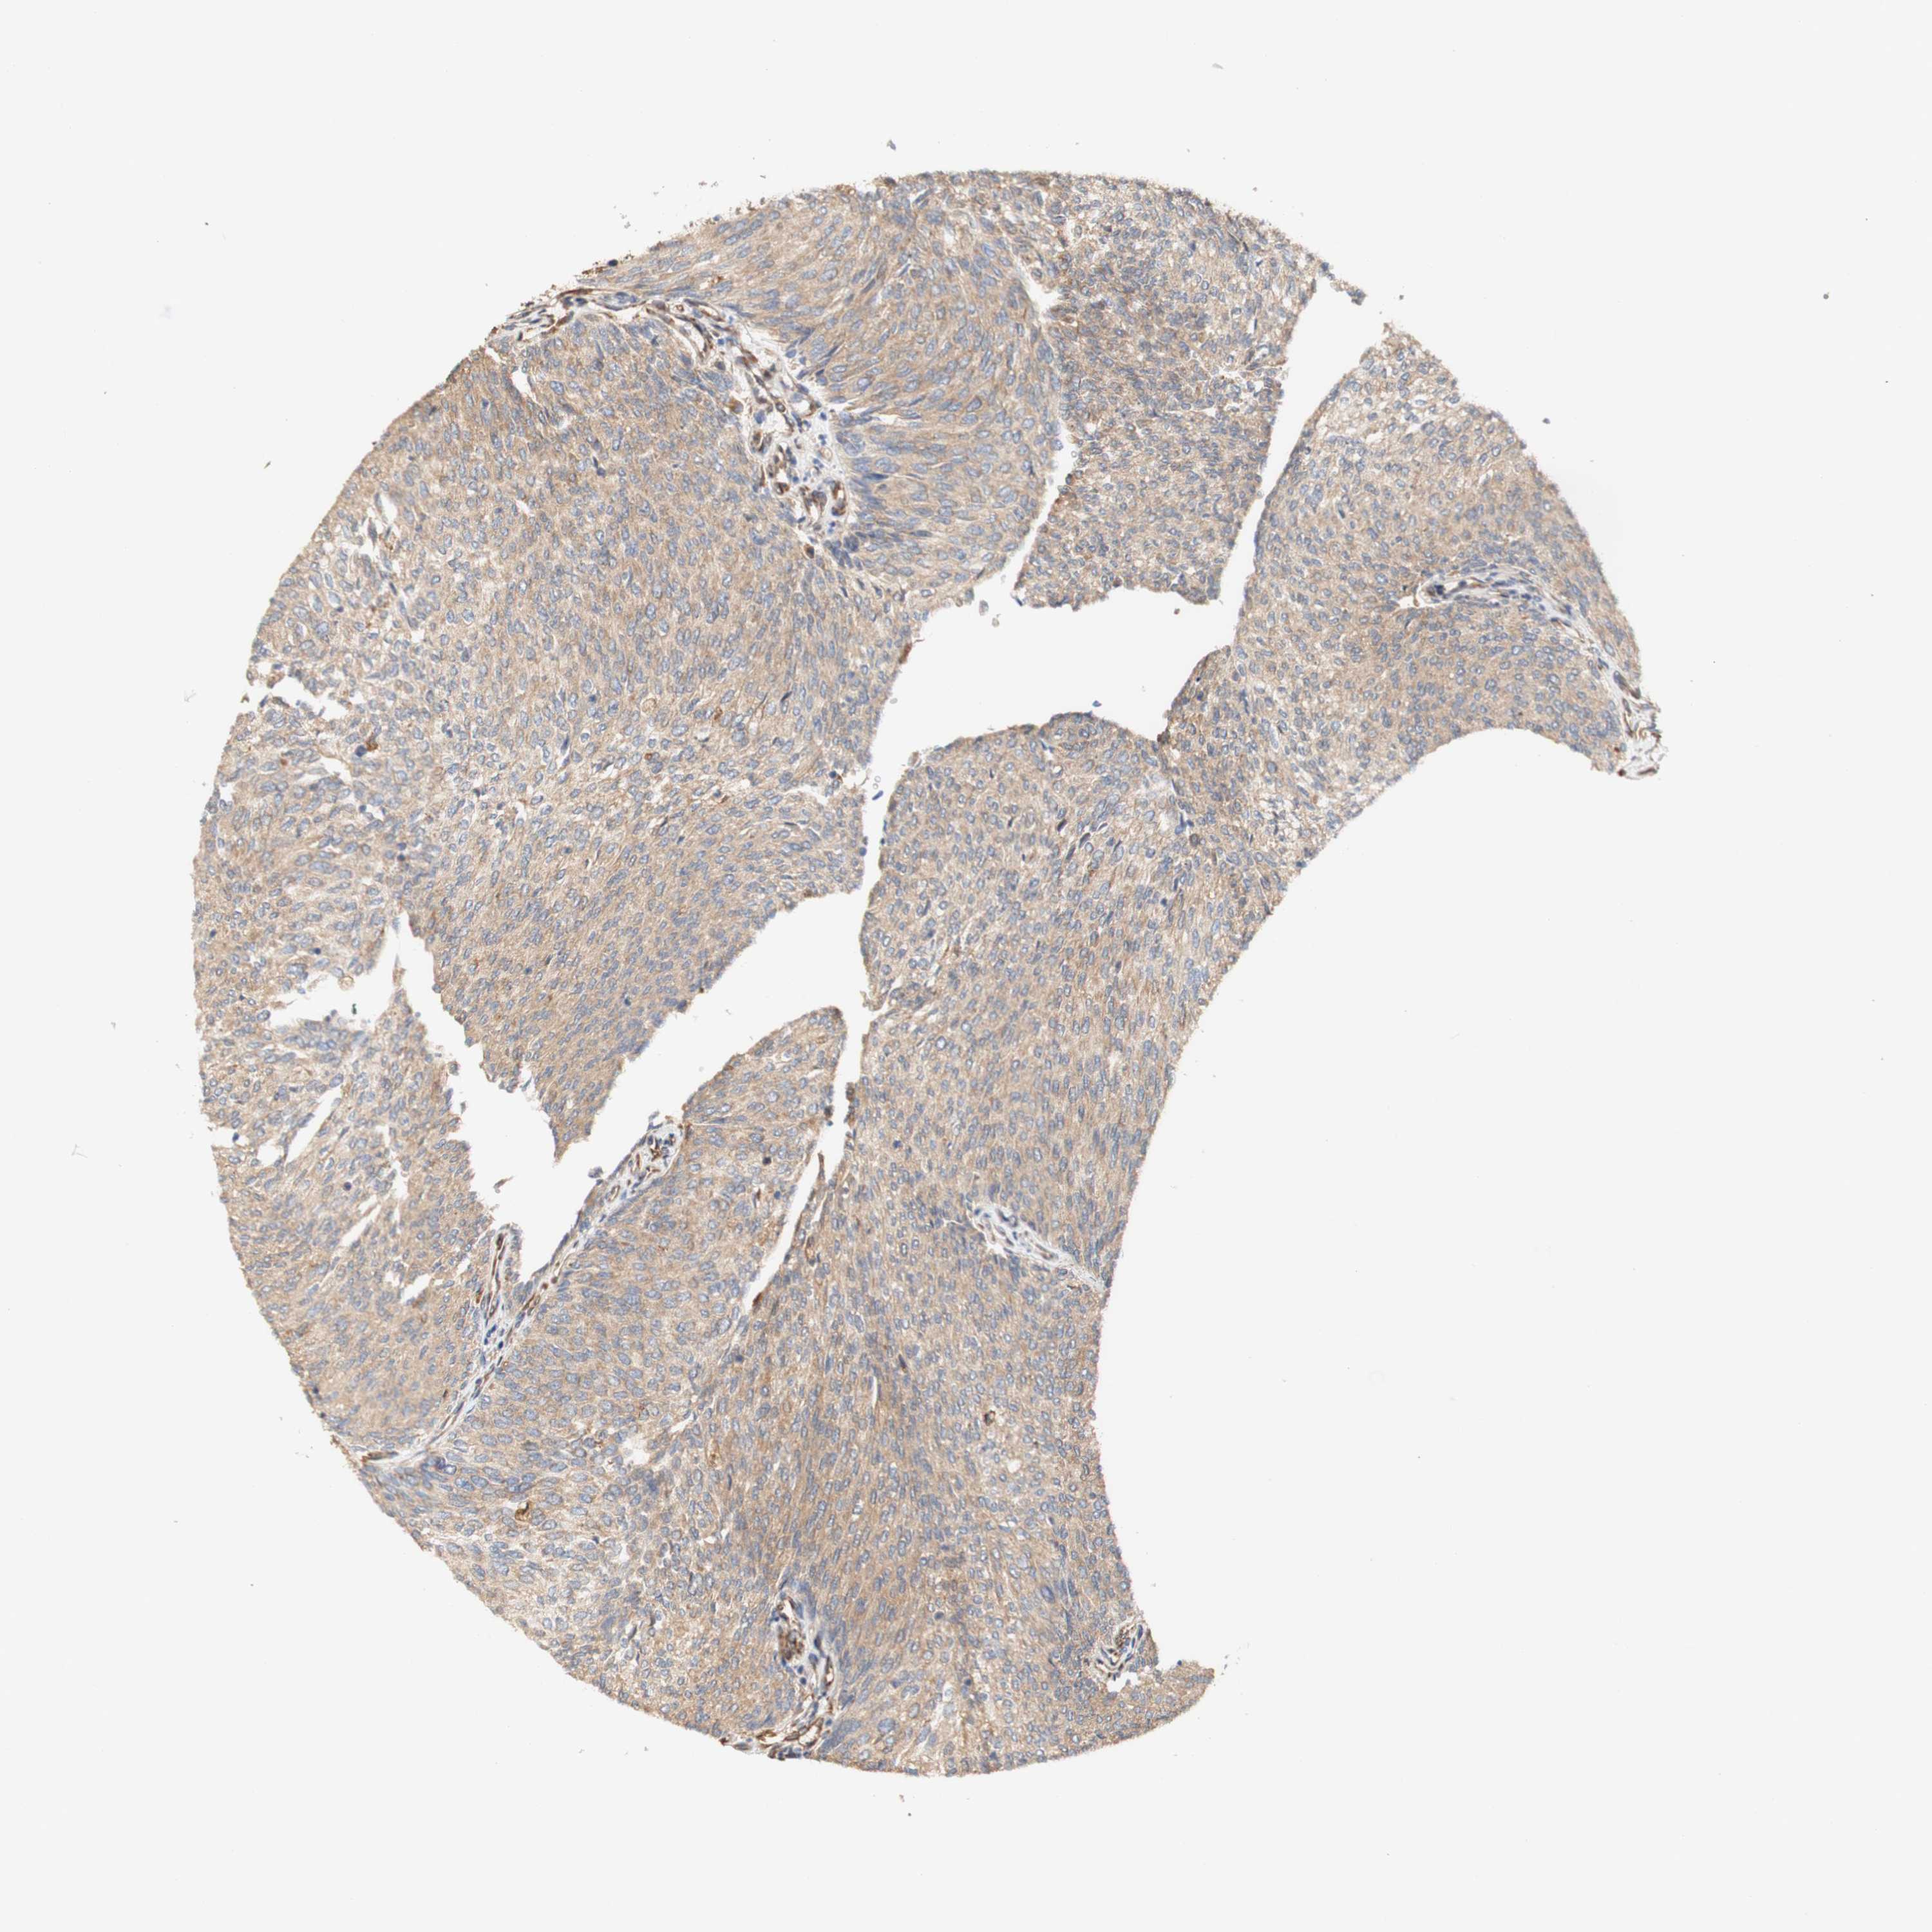

UROTHELIAL CANCER - Protein expressioni

A mouse-over function shows sample information and annotation data. Click on an image to view it in a full screen mode. Samples can be filtered based on level of antibody staining by selecting one or several of the following categories: high, medium, low and not detected. The assay and annotation is described here.

Note that samples used for immunohistochemistry by the Human Protein Atlas do not correspond to samples in the TCGA dataset.

Antibody stainingi

Antibody staining in the annotated cell types in the current human tissue is reported as not detected, low, medium, or high, based on conventional immunohistochemistry profiling in selected tissues. This score is based on the combination of the staining intensity and fraction of stained cells.

Each image is clickable and will lead to virtual microscopy that enables deeper exploration of all samples and also displays staining intensity scores, fraction scores and subcellular localization as well as patient and tissue information for each sample.

Antibody HPA011811

Staining

High

Medium

Low

Not detected

Intensity

Strong

Moderate

Weak

Negative

Quantity

>75%

75%-25%

<25%

None

Location

Nuclear

Cytoplasmic/membranous

Cytoplasmic/membranous,nuclear

Urothelial carcinoma, Low grade

Urothelial carcinoma, High grade